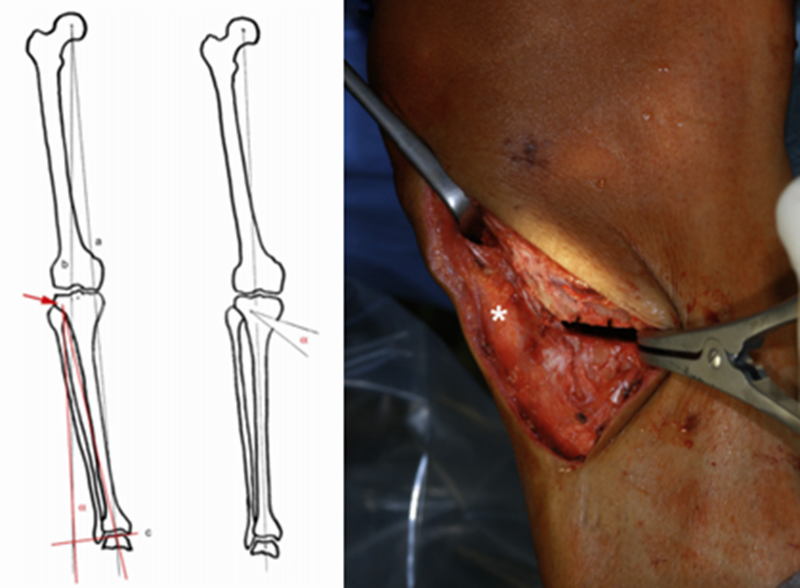

如何确定矫正度数

Coventry建议内翻畸形至少矫正至股骨胫骨解剖外翻角8°;Hernigou等发现患者术后机械外翻角在3°-6°时临床效果较好;Fujisawa等发现如果HTO术后力线通过胫骨外侧平台的30%-40%,软骨破坏则不再进展,若通过胫骨平台外侧的62%,则为最佳点,此点被定义为Fujisawa点。

A.双平面截骨,第一刀沿水平面在胫骨后2/3进行截骨,保留外侧合页约10mm,第二刀沿冠状面在胫骨前1/3进行截骨,两刀截骨角度呈110°。B.撑开器逐渐缓慢加大骨缝,注意保留外侧合页。C.力线杆定位,撑开至力线杆经过Fujisawa点。D.进行内固定。

CWHTO术前计划

北京积水潭医院黄野教授等采用改良外侧闭合楔形胫骨高位截骨术治疗24例共35膝年龄均在45岁以下的膝内翻伴膝关节内侧间室轻度骨关节炎患者,术后平均胫股角(FTA)173.6°±2.4°,平均矫正11.0°±4.3°,截骨端均愈合,有1例延迟愈合。术后半年完全负重,无一例发生感染。2例出现腓总神经并发症(5.7%)。

采用改良外侧闭合楔形截骨,可以安全有效纠正内翻畸形,缓解骨关节炎疼痛,适用于年轻活跃的单侧或双侧膝内翻患者。但腓骨截骨的并发症仍然是需要考虑的因素之一。